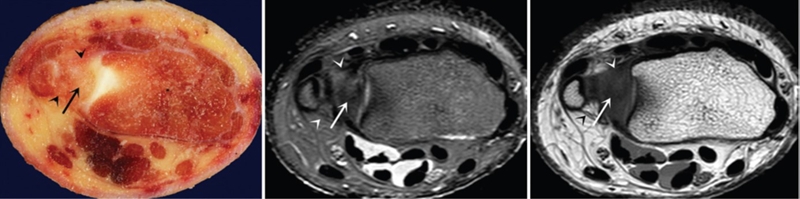

(2)MRI

ⅠA,TFCC中心穿孔,A、B三角软骨盘正常弓形低信号缺损;C轴位显示三角软骨盘中心的高信号区与D关节镜一致

ⅠB,TFCC尺侧撕裂;TFC尺侧附着处信号增高

ⅠC,尺三角韧带撕裂

ⅠD,TFC桡侧撕裂,桡侧附着处及桡尺关节处信号增高

ⅡA,TFC局部变薄,但结构完整

ⅡB,TFC局部变薄,但结构完整,月骨软骨厚薄不均

ⅡC,TFC中心撕裂,月骨软化,月三角韧带完整

ⅡD,TFC中心撕裂,月骨软化,月三角韧带缺如

图30 ⅡE,TFC中心撕裂,月骨、尺骨软骨软化,月三角韧带缺如,桡尺关节骨质增生